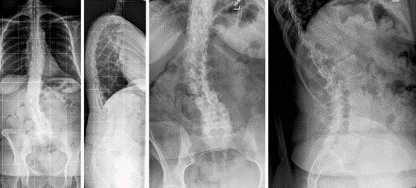

图5 脊柱远端融合节段越多,如包括L5-S1水平固定到骶骨或髂骨,发生交界性后凸的可能性越大

(2)上固定椎在交界区或存在交界性后凸

图6 长节段融合固定上固定椎(UIV)选择在胸10-12胸腰椎交界区是PJK的风险因素之一